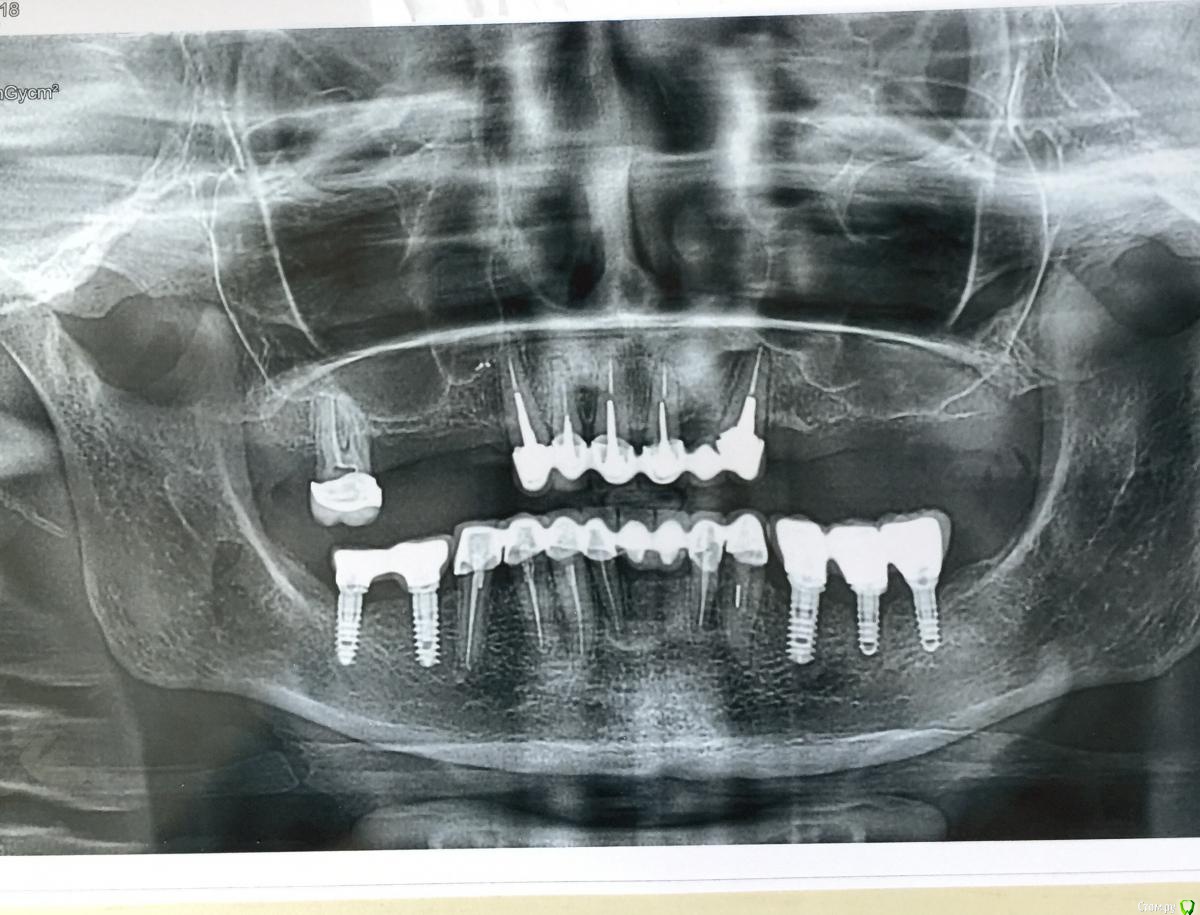

Mars12 Опубликовано 6 марта, 2018 Поделиться Опубликовано 6 марта, 2018 Здравствуйте!Ситуация такая: Внизу поставили импланты OT medical,сейчас предстоит синус лифтинг и врач предлагает туже систему имплантов, но у меня гложет сомнения,насколько эта система подходит в моем случаи, ( и вообще в выборе имплантов)что касается нижний челюсти, то уже поздно что-то менять...Ещё беспокоит 3 зуб слева , доктор говорит, что все хорошо и он не видит никаких причин (при нажатии неприятные ощущения, такое впечатление, что вкладка давит на корень и неприятный запах.Выскажите пожалуйста своё мнение по снимку! Ссылка на комментарий

колесников Опубликовано 6 марта, 2018 Поделиться Опубликовано 6 марта, 2018 Здравствуйте! Если вначале синуслифтинг,позднее имплантация,то можно и туже систему что и на н/ч ,если одномоментно-лучше рассмотреть другие. У 33 и 21 расцемениировка коронки как минимум. Ссылка на комментарий

колесников Опубликовано 6 марта, 2018 Поделиться Опубликовано 6 марта, 2018 Вероятно резорцинен. Канал склерозирован,в канале фрактура инструмента,но в периапикальных тканях без патологии . Есть подозрение на расцемениировку и размягчение культи. Надо снимать коронку и делать ревизию Ссылка на комментарий

Mars12 Опубликовано 7 марта, 2018 Автор Поделиться Опубликовано 7 марта, 2018 Вероятно резорцинен. Канал склерозирован,в канале фрактура инструмента,но в периапикальных тканях без патологии . Есть подозрение на расцемениировку и размягчение культи. Надо снимать коронку и делать ревизиюСпасибо!Я имела ввиду верхний клык , не знаю как правильно определить сторону, с противоположной стороны от семёрки.Что можете сказать по этому поводу? Врач заверяет, что все хорошо, но факт на лицо, неприятные ощущения при надавливании и запах. Ссылка на комментарий